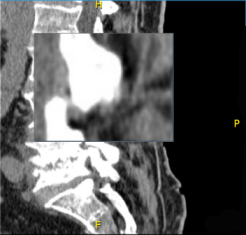

- Μετακινήστε τον δείκτη του ποντικιού σας επάνω στην οθόνη και μετά κάντε κλικ παρατεταμένα για εμφάνιση του εργαλείου μεγεθυντικού φακού.

Εμφανίζεται ένα παράθυρο προβολής όπου προβάλλεται η επιλεγμένη περιοχή σε αυξημένη μεγέθυνση.